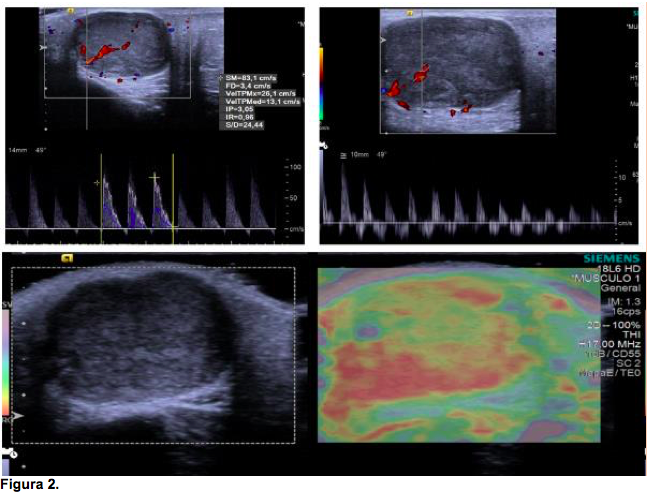

En la radiografía anteroposterior y lateral de cráneo no se observaron alteraciones intrínsecas en las estructuras óseas del cráneo y de la cara ni calcificaciones. Se realizó ultrasonido en escala de grises con aplicación de Doppler color (figura 1), en el que se describió una lesión nodular de 24.3 x 22.6 x 17.6 mm con un volumen de 5.1 cc, sólida, de baja rigidez demostrada por elastografía y altamente vascularizada en tejido celular subcutáneo de la región malar izquierda (figura 2).